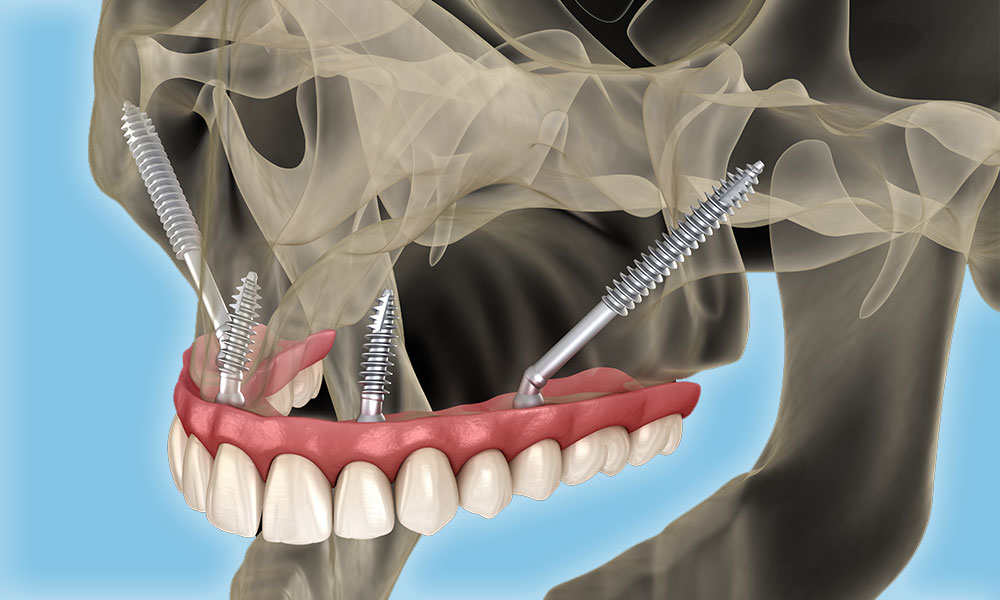

3. Zygomatic Implants

Zygomatic implants are a subtype of endosteal. They constitute another feasible alternative for patients lacking sufficient bone. This is because they are much longer than the standard endosteal and can be solidly implanted in the upper jaw bone (zygoma).